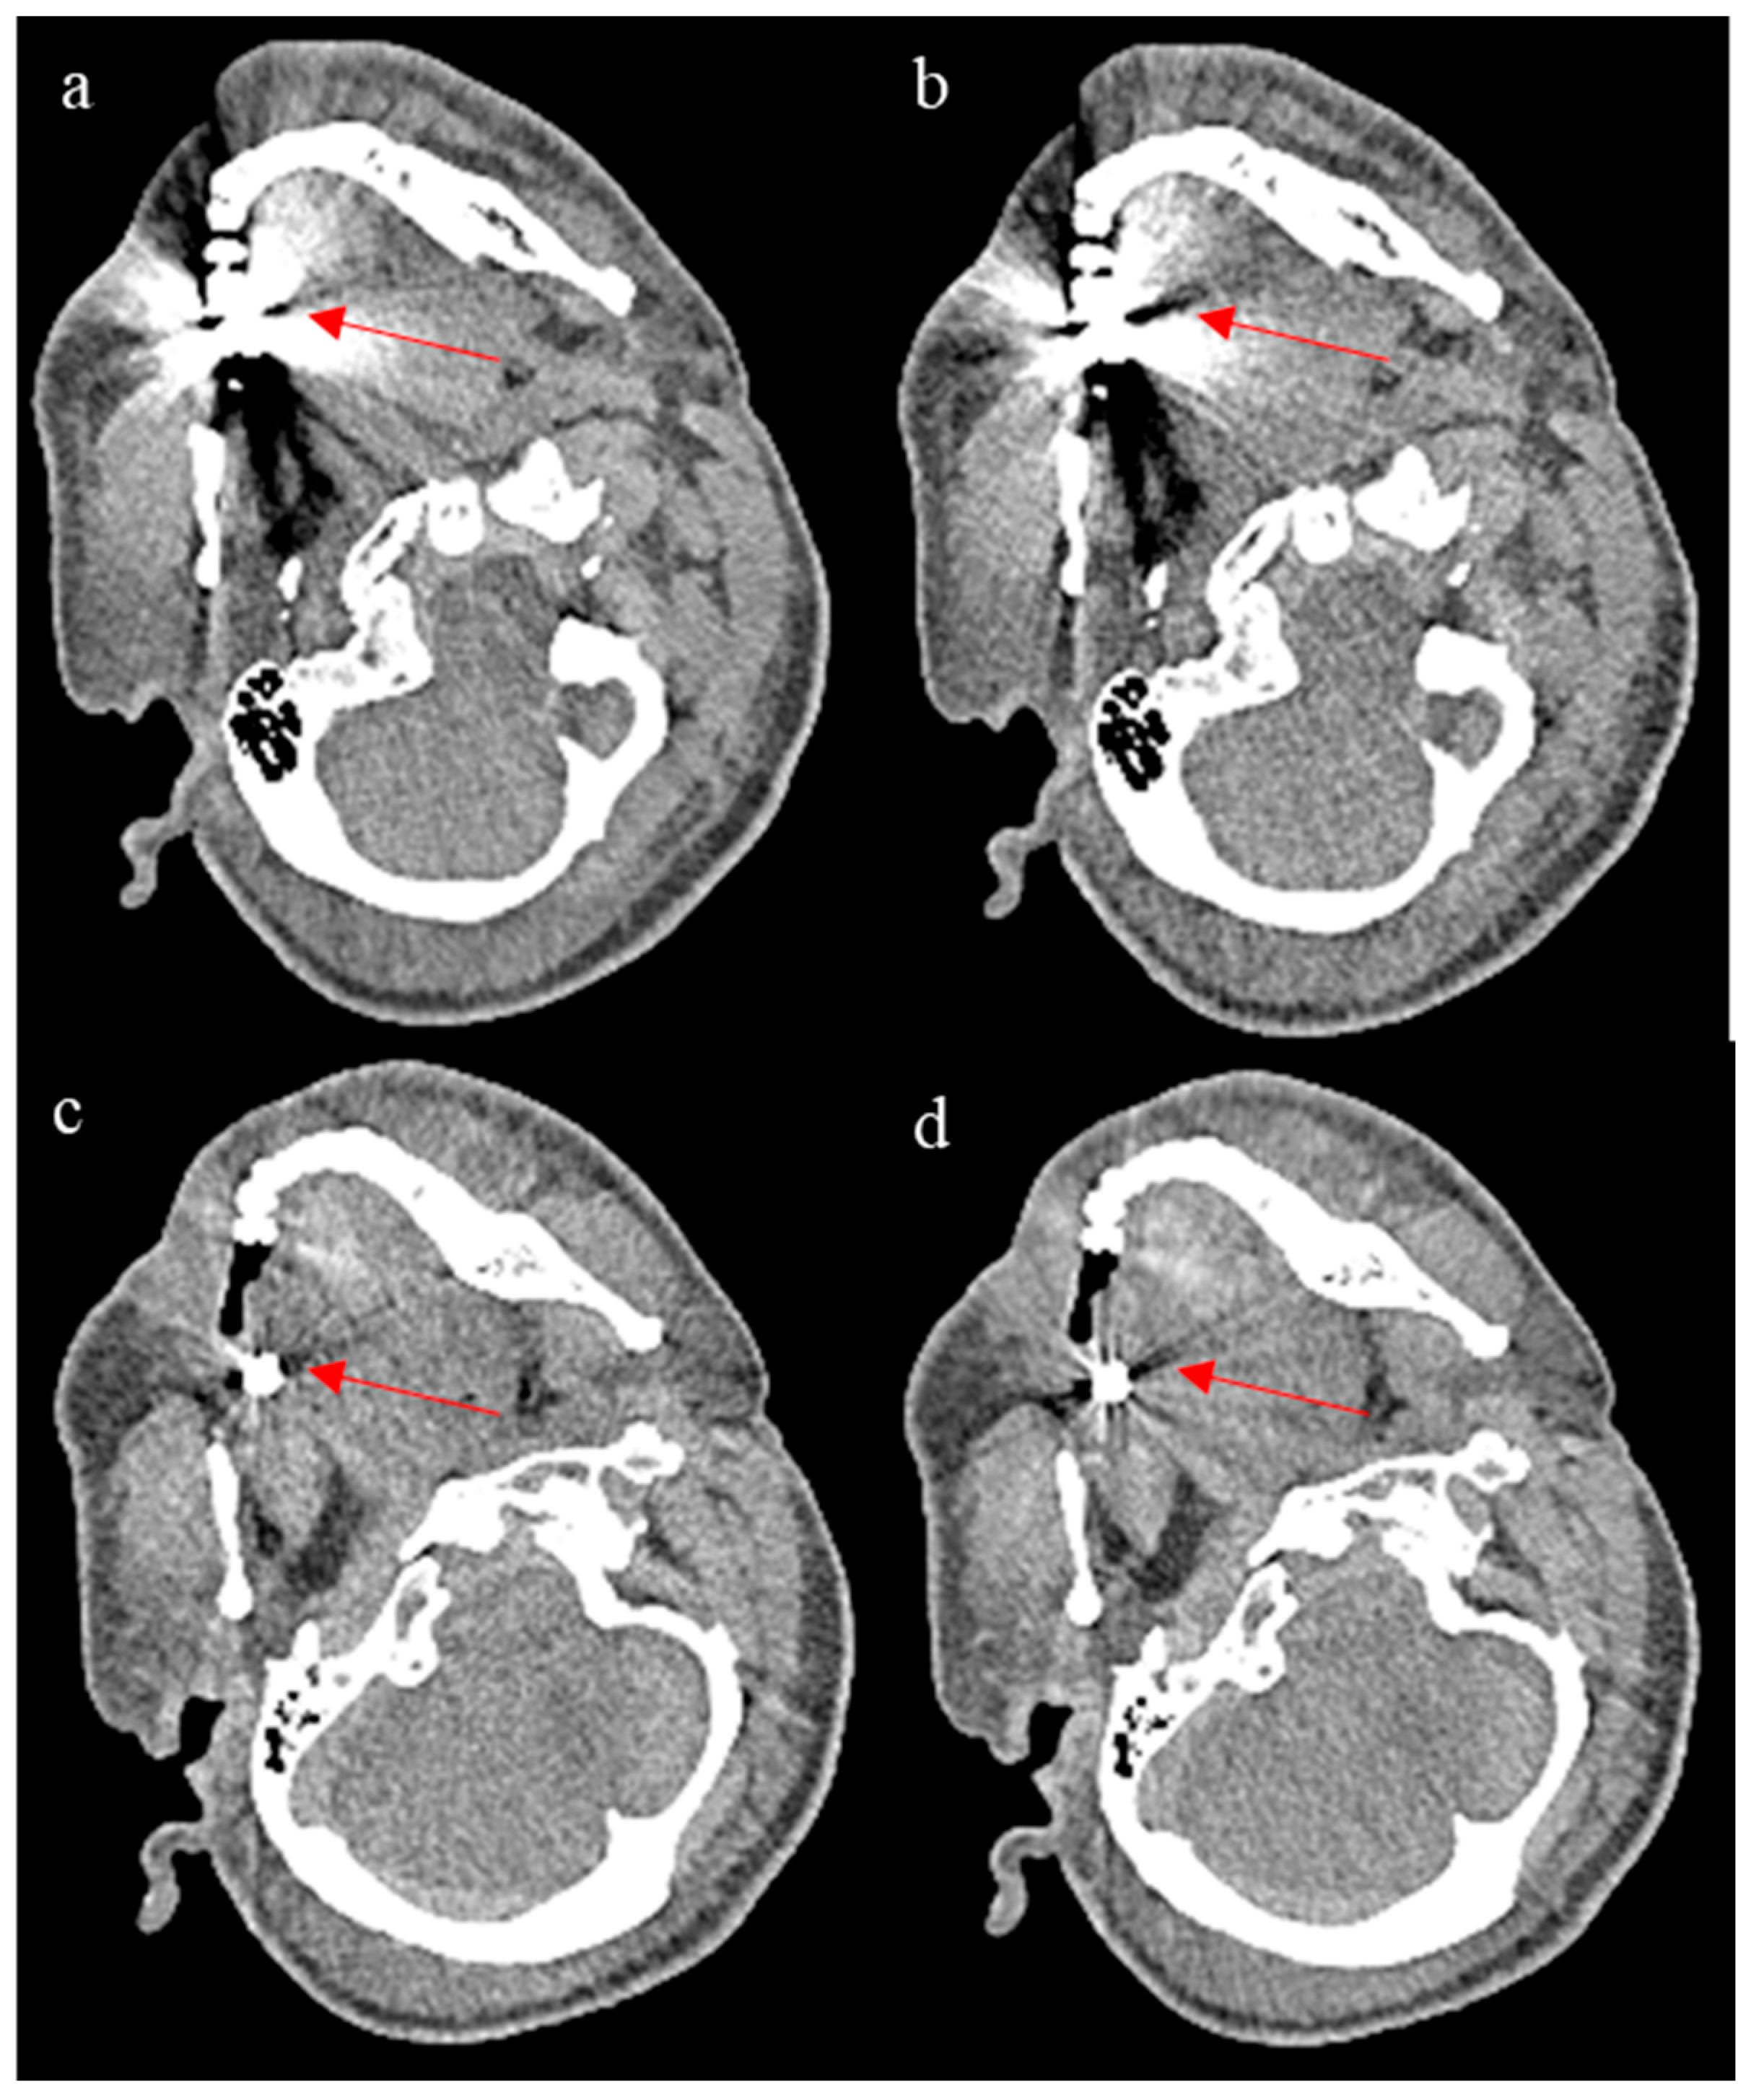

To evaluate ErisNet’s behaviour in complex clinical scenarios, Figure 7 illustrates the model’s performance on CT images containing metal artefacts. It should be noted that the training dataset contained a limited number of cases with metal implants, which may be insufficient to allow the model to learn optimal denoising strategies in the presence of such artefacts. The results reported here suggest inconsistent performance, with the network appearing to respond differently depending on the extent of the metal artefacts present. These results indicate that the reliability of the model in cases with significant metal artefacts remains uncertain and would require dedicated training with a more representative dataset of metal artefact cases to achieve consistent clinical performance.

Figure 7.

The figure shows ErisNet’s performance on CT images containing metallic artefacts. (a,c) are images processed with ErisNet showing noise reduction compared to the corresponding low-dose inputs (b,d), respectively. The red arrows highlight specific regions where noise reduction in metal artefacts can be appreciated in the processed images. Although both cases (a,c) show some degree of noise reduction, as indicated by the arrows, the extent and quality of the improvement vary between the two scenarios.